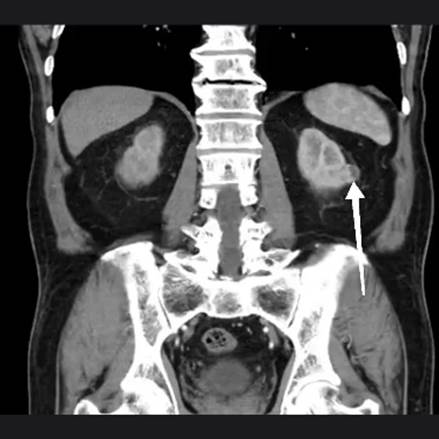

Como antecedentes personales patológicos padece hipertensión arterial sistémica debutante e identificada al ingreso, negando otras enfermedades incluyendo antecedentes quirúrgicos. Inicia su padecimiento con hematuria macroscópica no formadora de coágulos de larga evolución que condiciona síndrome anémico caracterizado por astenia y adinamia, así como palidez de tegumentos. Acude a valoración por área de urgencias donde se le solicitan laboratorios incluyendo biometría hemática (hemoglobina inicial 8.9 g/dL) y urotomografía como parte del protocolo de estudio; en dicha tomografía se muestran imágenes en relación a tumor urotelial en cavidades renales derechas, así como tumor renal izquierdo clasificado como T1a (Imagen 1 y 2).

Unidad renal izquierda con imagen sugerente de tumoración parenquimatosa ipsilateral en borde lateral cercana a la línea interpolar (flecha blanca gruesa).

Imagen 2 Urotomografía en corte coronal